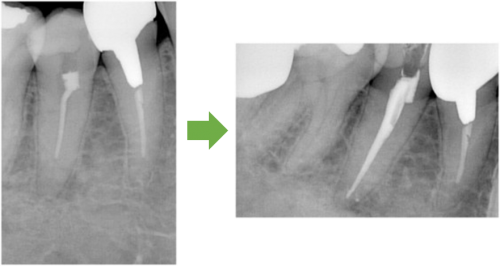

根の管を拡げ終えました→症状がなくなりました→最終的なお薬を詰めます

土台の型を取ります→土台を付けます

歯の周りを削ります→被せ物を付けます